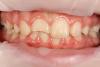

Diamondus Опубликовано 17 января, 2013 Поделиться Опубликовано 17 января, 2013 Девочка 9 лет. Скол вследствие травмы. Апекальная часть не сформирована. Детский врач направила для изготовления металлической штампованной коронки. Сказала, что после формирования верхушки (после 12 лет) заменить на композитную реставрацию. А сейчас композитную реставрацию проводить нельзя, есть возможность получить пульпит. На дентин только стеклоиномер. Пробовал перекрывать дентин стеклоиномером, эмаль композитом. Но все выпадает. Решил поставить керамический винир без препарирования. Ваше мнение в данной ситуации? Ссылка на комментарий